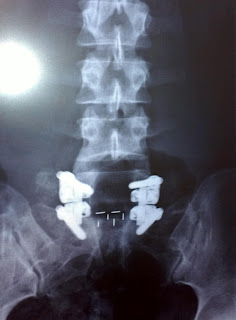

I wanted to post in monthly so I'm a little late, but today I am 2 months 1 week post op of my L5-S1 (PLIF) Spinal Fusion. The last time I posted, I got my back brace off, saw my surgeon, and was waiting to start physical therapy. I am happy to say that I (surprisingly) did not have to fight the insurance to approve my physical therapy and I started with no delays. I love the place I go to, and my physical therapist. We are going at a very slow pace and I am completely fine with that! When he first evaluated me, he said that my range of motion was good except my hamstrings were very limited to movement. My sessions usually are about an hour to an hour and a half long and it usually goes like this:

My surgeon also said to try and only sit for 15 minutes at a time, which seems a little unrealistic to me, but I try to get up and walk around frequently. The car is getting a little bit easier. Sneezing is still my worst enemy, very very painful. Walking long distances gets hard, but in general, I am able to walk a lot more than I was able to before surgery. I vaccumed and did light cleaning the other day, and was a little sore, but very excited I was able to do it being that I haven't in so long. I am barely taking any medicines anymore, not even tylenol, unless its a bad day. I tried to sit through my brothers graduation and that was very painful, but that is all part of learning your limits and knowing how long you can and can't do certain things. That does not mean I'm pain free, that means that I am able to bare it and deal with the pain, which I am happy with. There is still a long way to go, and I am still feeling a good amount of pain, but overall, I am happy with the surgery so far and only time will tell everything else. I see my surgeon next June 13th I believe, so I will definitely post in after that as well. Any questions or anything feel free to comment, or e-mail me. Post back soon =] Happy Memorials Day everyone!